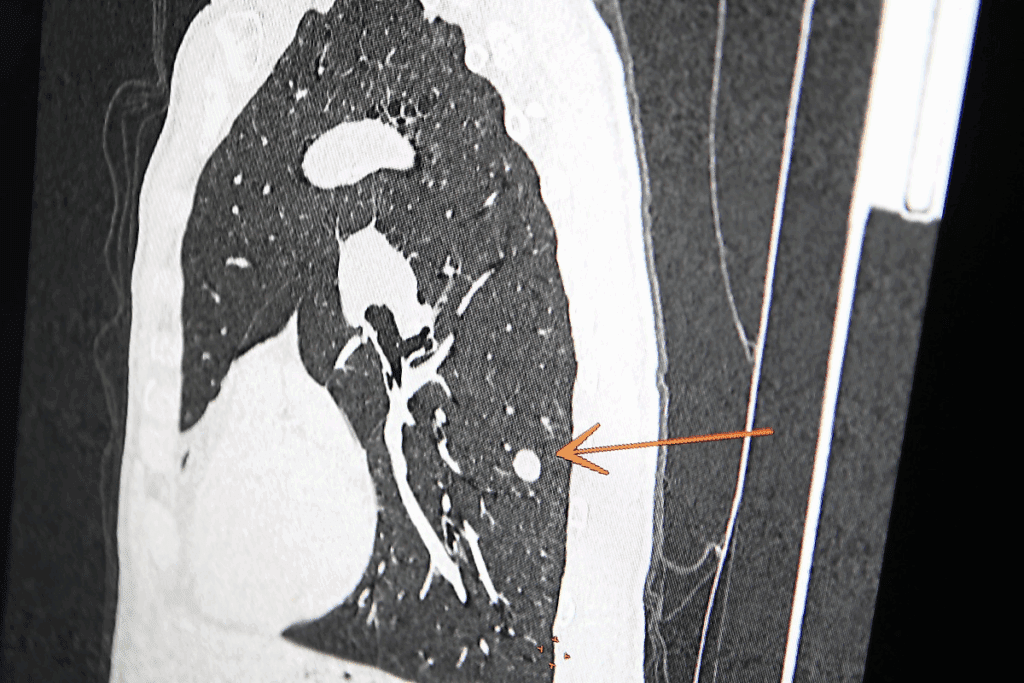

Lung nodules are often seen in chest scans. Knowing what they are helps doctors decide what to do next. They can be found with CT scans, X-rays, and MRIs.

CT scans are key in this planning. They show us the nodule’s size, where it is, and if it might be cancer. These images help us decide the best way to do the biopsy.

Both CT and ultrasound guidance help place the needle accurately during biopsy. CT guidance is great for nodules hard to see with ultrasound. It provides detailed images. Ultrasound guidance offers real-time imaging without radiation, making it a good alternative for some cases.

Imaging studies like CT scans are key before a biopsy. They help find the nodule, check its size, and plan the biopsy.